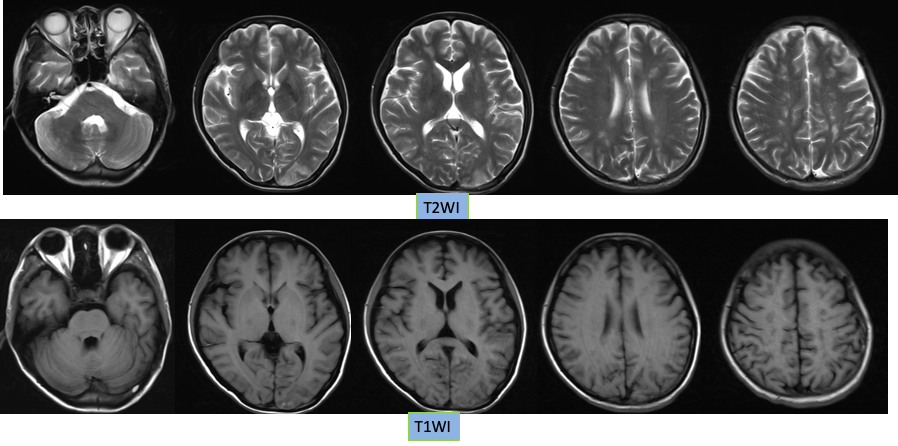

1. 本病例影像学表现提示的诊断线索:青年女性,脑内新见散在多发病灶,散在分布于多个脑动脉供血区,包括幕上幕下,皮层及深部白质,无明显占位效应,病灶周围无水肿,弥散受限,增强扫描左枕叶较大病灶不均匀强化,余病灶无明显强化。

定性诊断:本病例特点为青年女性,有明确肺癌病史,无明确神经系统症状,CT 发现颅内新发多发病灶,结合病史首先不除外转移瘤,MR 进一步检查病灶符合多发急性期脑梗死,确诊脑梗死不难,难的是确认脑梗死的发病原因。

典型影像学表现:DWI 上病灶累及 3 个或 3 个以上血管分布区,常累及前后循环,双侧多见。排除其他明确的栓塞源或与这些病变相关的其他疾病。